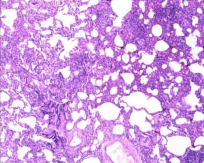

肺组织病理中,非纤维化型HP包括细胞性间质性肺炎(可见细支气管中心性分布,细胞性NSIP型,以淋巴细胞为著)、细胞性细支气管炎、未形成非坏死性肉芽肿(与结节病的肉芽肿呈显著差别)。纤维化型HP包括慢性纤维化性间质性肺炎(结构扭曲、成纤维细胞灶±胸膜下蜂窝肺纤维化性NSIP型)、气道中心性纤维化。

比如细胞性细支气管炎(下图左),可以看到很多淋巴细胞浸润;还有非坏死性肉芽肿炎(下图中),肉芽肿的边界并不清楚,有一些内上皮细胞和炎症浸润;细胞性慢性间质性肺炎——「NSIP样改变」(下图右)。